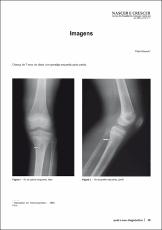

Imagens: Defeito cortical da tíbia.

Nascer e Crescer 2006; 15(1): 39-40